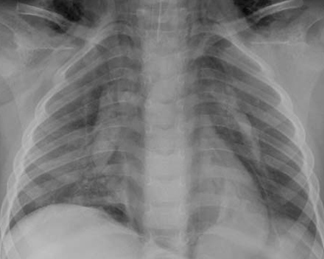

Doença da membrana hialina (síndrome do desconforto respiratório tipo 1): broncogramas aéreos e um padrão retículo-granular

Do acervo de Ponthenkandath Sasidharan, MD; usado com permissão